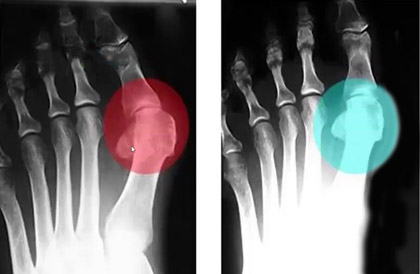

До использования

После 1,5 месяца использования шины FootRelax